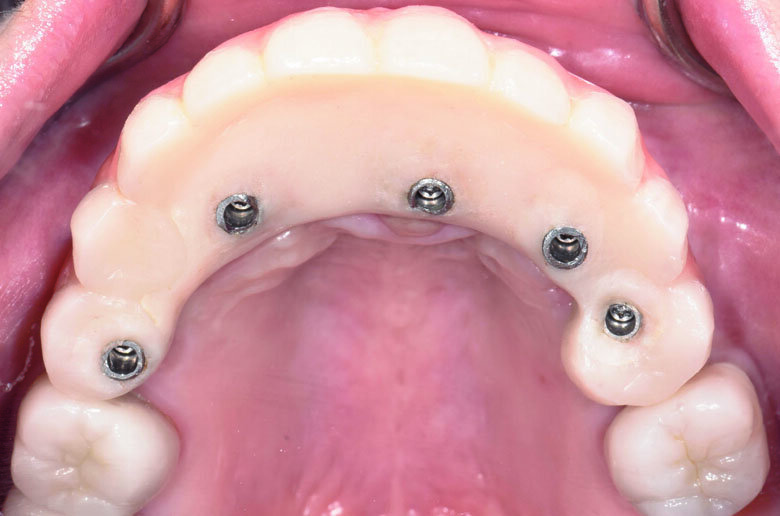

Fig 23. Post-operative occlusal view

The questionable teeth (13, 24 and 25) were extracted under local anaesthesia. The surgical guide was secured in place on the maxillary arch with two anchor pins. (Figs. 21) Flapless surgery was performed using guided tissue punch. Sequential drilling were made according to the manufacturer’s protocol. All implants were placed through the surgical template. All implants were torqued 35 NCm to ensure primary stability. The extraction socket were filled with small particle Xenograft (Bio-Oss, Geistlich) and covered with resorbable collagen plug (Collar plug, Zimmer Biomet). Straight and angle multi-unit abutments were seated and torqued 15 NCm on each implants (Fig. 23)

The existing provisional bridge was utilized for converting to a provisional screw-retained prosthesis. An immediate loading protocol was utilised2. Metal temporary abutments were connected on each implant. Provisional full arch bridge was perforated to match the position of the metal temporary abutments, placed in their correct position and OVD, relined with self-cure acrylic resin. All surfaces were fine-polished. A light-cure denture sealant (Palaseal, Kulzer) was applied on the intaglio surface. The provisional bridge was delivered to the patient’s mouth. (Figs. 23-27) Post-operative panoramic XRAY revealed that implants were placed according to the pre-operative planning (Fig. 22) Suture was removed after surgery 14 days. A final profile protheses3 will be fabricated after implant osseointegration.